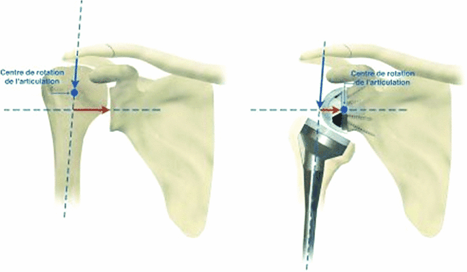

Het pijnprobleem wordt opgelost door nieuwe gewrichtsoppervlaktes, het krachtsverlies en pseudo verlamming door een veranderde mechaniek in de schouder met verleggen van rotatiepunten en krachtsarmen.

Zo zijn we in staat om een schouder te maken die geen pijn doet en toch een zeer behoorlijke functie geeft. Welliswaar niet met dezelfde kracht als van een twintigjarige maar voldoende om meer dan de dagdagelijkse behoeften te dekken.

Tijdens de ingreep worden de pan en de bol van plaats gewisseld. Vandaar de naam omgekeerde prothese.